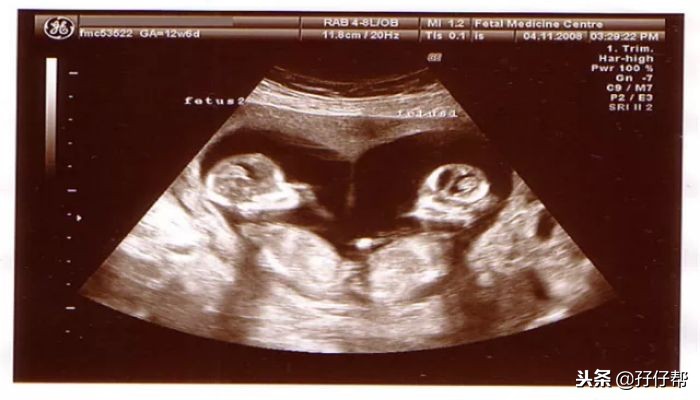

B超孕12周的双胞胎胎儿影像图⏬⏬: